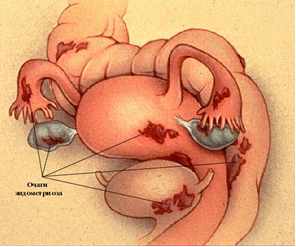

Эндометриоз — болезнь, которая встречается у женщин репродуктивного возраста, то есть в период их способности к деторождению (рис. 4). Она проявляется разрастанием ткани, похожей на эндометрий, за пределами внутренней поверхности матки.

В зависимости от локализации очагов эндометриоз бывает генитальным и экстрагенитальным. Генитальный эндометриоз встречается чаще, и в этих случаях поражаются женские половые органы (брюшина малого таза, связки матки, яичники, маточные трубы, стенки матки и шейка матки). Если очаги эндометриоза находятся за пределами половой сферы, то такой эндометриоз называют экстрагенитальным. Наиболее часто эндометриозом поражаются мочевой пузырь, мочеточники, кишечник, реже — легкие, бронхи, печень.

Рис. 4. Эндометриоз органов малого таза

Если очаги эндометриоза локализуются на маточных трубах, яичниках, на брюшине малого таза, кровянистые выделения из этих очагов попадают в брюшную полость, вызывают воспалительную реакцию тканей, что приводит к формированию спаек и непроходимости маточных труб. Эндометриоз нередко (в 17–27% случаев) сопровождается нарушением созревания фолликулов, ановуляцией и недостаточностью желтого тела.